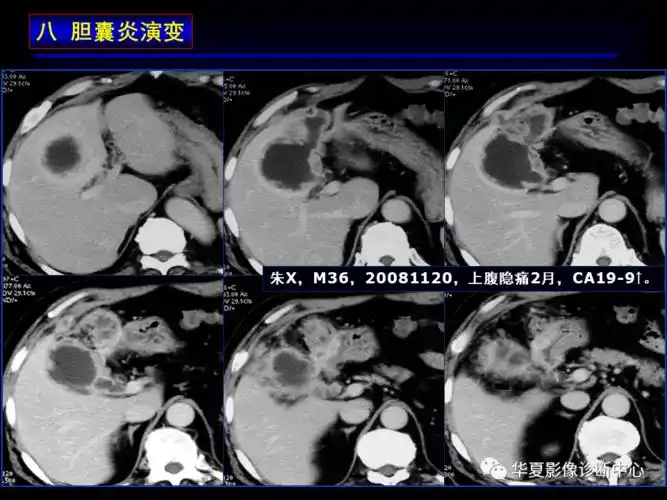

慢性胆囊炎并胆囊结石ct病例图片影像诊断分析

胆囊炎影像诊断